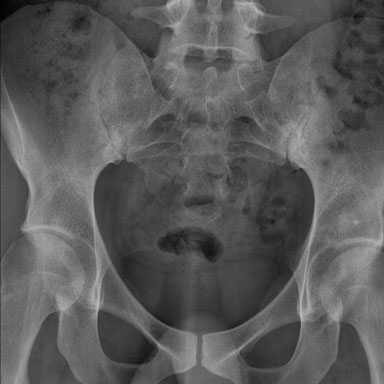

X-quang

Xơ cứng dưới sụn và bào mòn hai bên khớp cùng chậu do viêm khớp cùng chậu.

Chẩn đoán phân biệt viêm khớp cùng chậu:

- Thoái hóa khớp: xơ cứng dưới sụn hai bên khớp cùng chậu không kèm bào mòn.

- Viêm xương đặc xương chậu (Osteitis condensans ilii): xơ cứng hình tam giác hai bên ở xương chậu tiếp giáp với khớp cùng chậu.

Chẩn đoán viêm khớp cùng chậu có thể gặp khó khăn khi chỉ dựa vào X-quang. Việc bổ sung X-quang cột sống thắt lưng hoặc các phương tiện chẩn đoán khác có thể giúp tăng độ chắc chắn trong chẩn đoán.

Viêm khớp cùng chậu giai đoạn muộn với dính khớp cùng chậu.